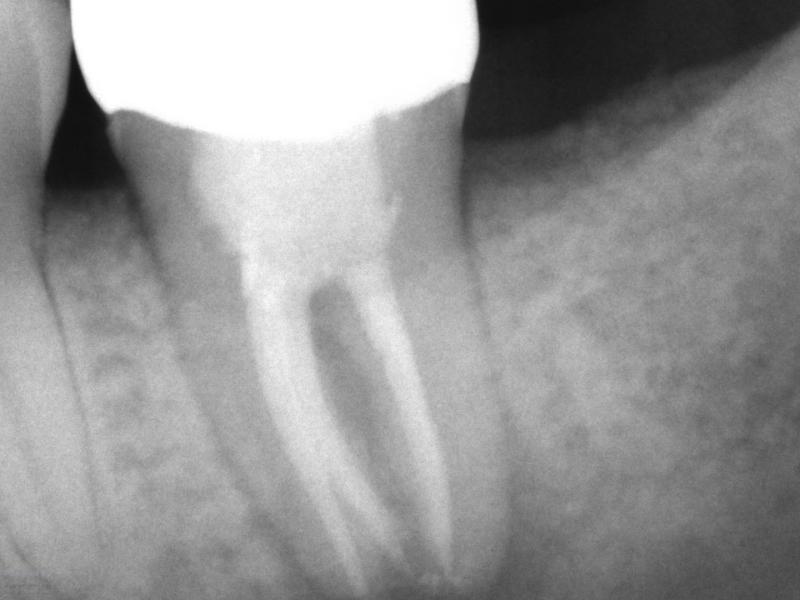

Post-Op